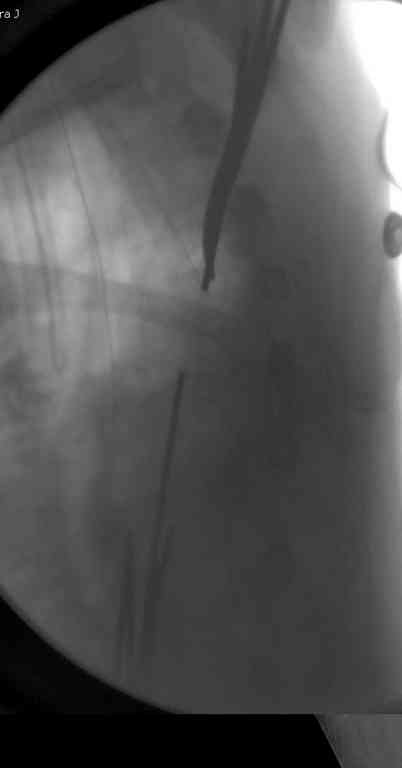

Сделали напряженными спицами по методике А.Ф.Лазарева со товарищи Репозиция сделана спицевым дистрактором, проксимальная спица была проведена в полскости деформации перпендикулярно оси наклонившейся головки. Получилось все довольно легко. Спицы малость покороче можно было сделать, ну да удалять потом легче будет.

Картинка в приложении.

Очень даже неплохо получилось. Молодцы! Лучше чем на 3D "репозиции".

Все заняло 1 час. Собственно введение фиксаторов - минут 20.

Оставили в косынке, сразу разрешены маятникообразные движения в плечевом суставе. Дальше по ходу расскажу.